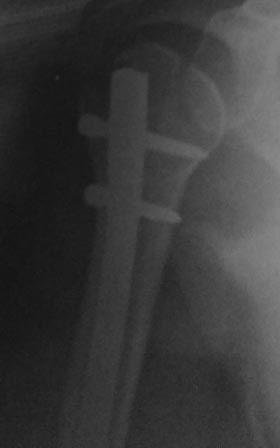

Диагноз - Спиральный перелом н/з диафиза правой плечевой кости со смещениемк к/отломков. Обширные геморрагические пузыри с-н/3 плеча. Ожирение 2 степени. ИБС. Стенокардия напряжения. Гипертоническая болезнь 2-ст.

Операция 16.03.17г. БИОС закрытым способом СhM под ЭОП.В ходе рассверливания к/м канала дистального отломка, видимо, имеющийся осколок откололся , но стояние было удовлетворительное, в конце операции при контрольной проверке под ЭОП все было нормально (см.снимки под ЭОП).

На контрольной Р-грамме на следующий день – осколок сместился. Коллеги рекомендуют или щилом втолкнуть, или маленьким разрезом открыть и репонировать, и т.д.